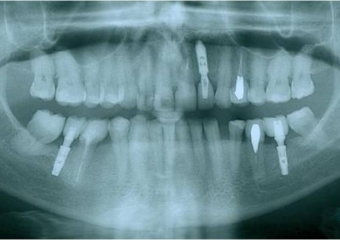

Raio X inicial